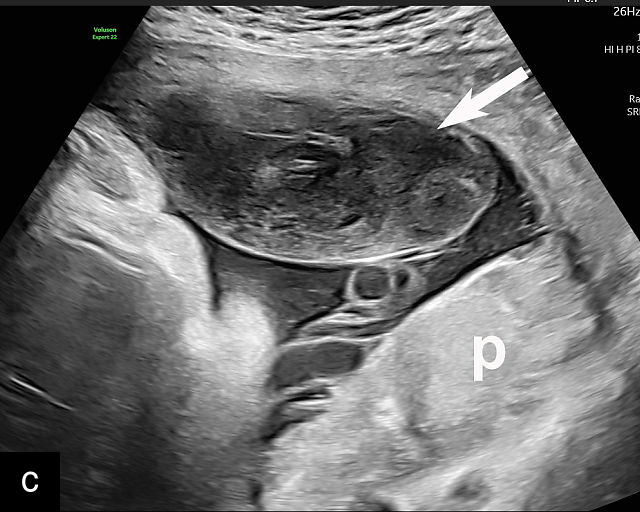

6

Placenta accreta spectrum. (a,b) Sagittal transabdominal grayscale ultrasound of the lower uterus and cervix demonstrating placenta previa accreta, with the placenta (p) containing prominent irregular hypoechoic lacunae. There is absence of the myometrium at the bladder (b) interface (arrows) c, cervix. (c) Sagittal transabdominal color Doppler ultrasound of the lower uterus and cervix demonstrating placenta previa accreta, with increased vascularity of the lower uterus and the myometrial bladder interface. (d) Transvaginal ultrasound of placenta previa accreta showing multiple lacunae involving the cervix with no clear demarcation between the placenta and the cervix. (e) Transvaginal ultrasound of placenta previa accreta showing multiple large irregular lacunae involving the cervix with no clear demarcation between the placenta (p) and the cervix. The placenta has a ‘moth-eaten’ appearance. There is loss of myometrium (arrows). (f) Transvaginal ultrasound of placenta previa accreta without and with color flow Doppler showing multiple large irregular lacunae. The placenta has a ‘moth-eaten’ appearance. There is hypervascularity of the myometrial interface. (g) Transvaginal ultrasound of placenta previa accreta showing multiple lacunae involving the cervix with no clear demarcation between the placenta and the cervix. (h) Transvaginal ultrasound of placenta previa accreta with color flow Doppler showing hypervascularity of the myometrial interface and irregularity of the bladder wall. b, bladder; p, placenta. (i) Transabdominal grayscale ultrasound of cesarean scar pregnancy. The uterine fundus (f) is empty (arrowhead). The gestational sac (arrow) is located in the lower uterus, anterior to the uterine canal, and lies above the cervix (c). b, bladder. (j) Transvaginal grayscale ultrasound image of cesarean scar pregnancy showing the empty fundus (f) and the normal cervix (c). The gestational sac lies below the fundus, above the cervix and anterior to the uterine cavity. (k) Transvaginal grayscale ultrasound image of cesarean scar pregnancy showing the empty cavity (arrowheads) of the uterine fundus (f), and the normal cervix (c). The gestational sac lies below the fundus, above the cervix and anterior to the uterine cavity (arrow).

Several characteristic sonographic findings are associated with PAS.90,95,96,97 These include placental lacunae, which appear as hypoechoic, irregular spaces within the placenta with high-velocity turbulent flow on color Doppler.16,50 Other features include obliteration of the retroplacental clear space, thinning of the myometrium in the lower uterine segment, irregularity and hypervascularity of the myometrial–bladder interface, and placental bulging into the bladder (Figure 6a–h).90,96,98,99